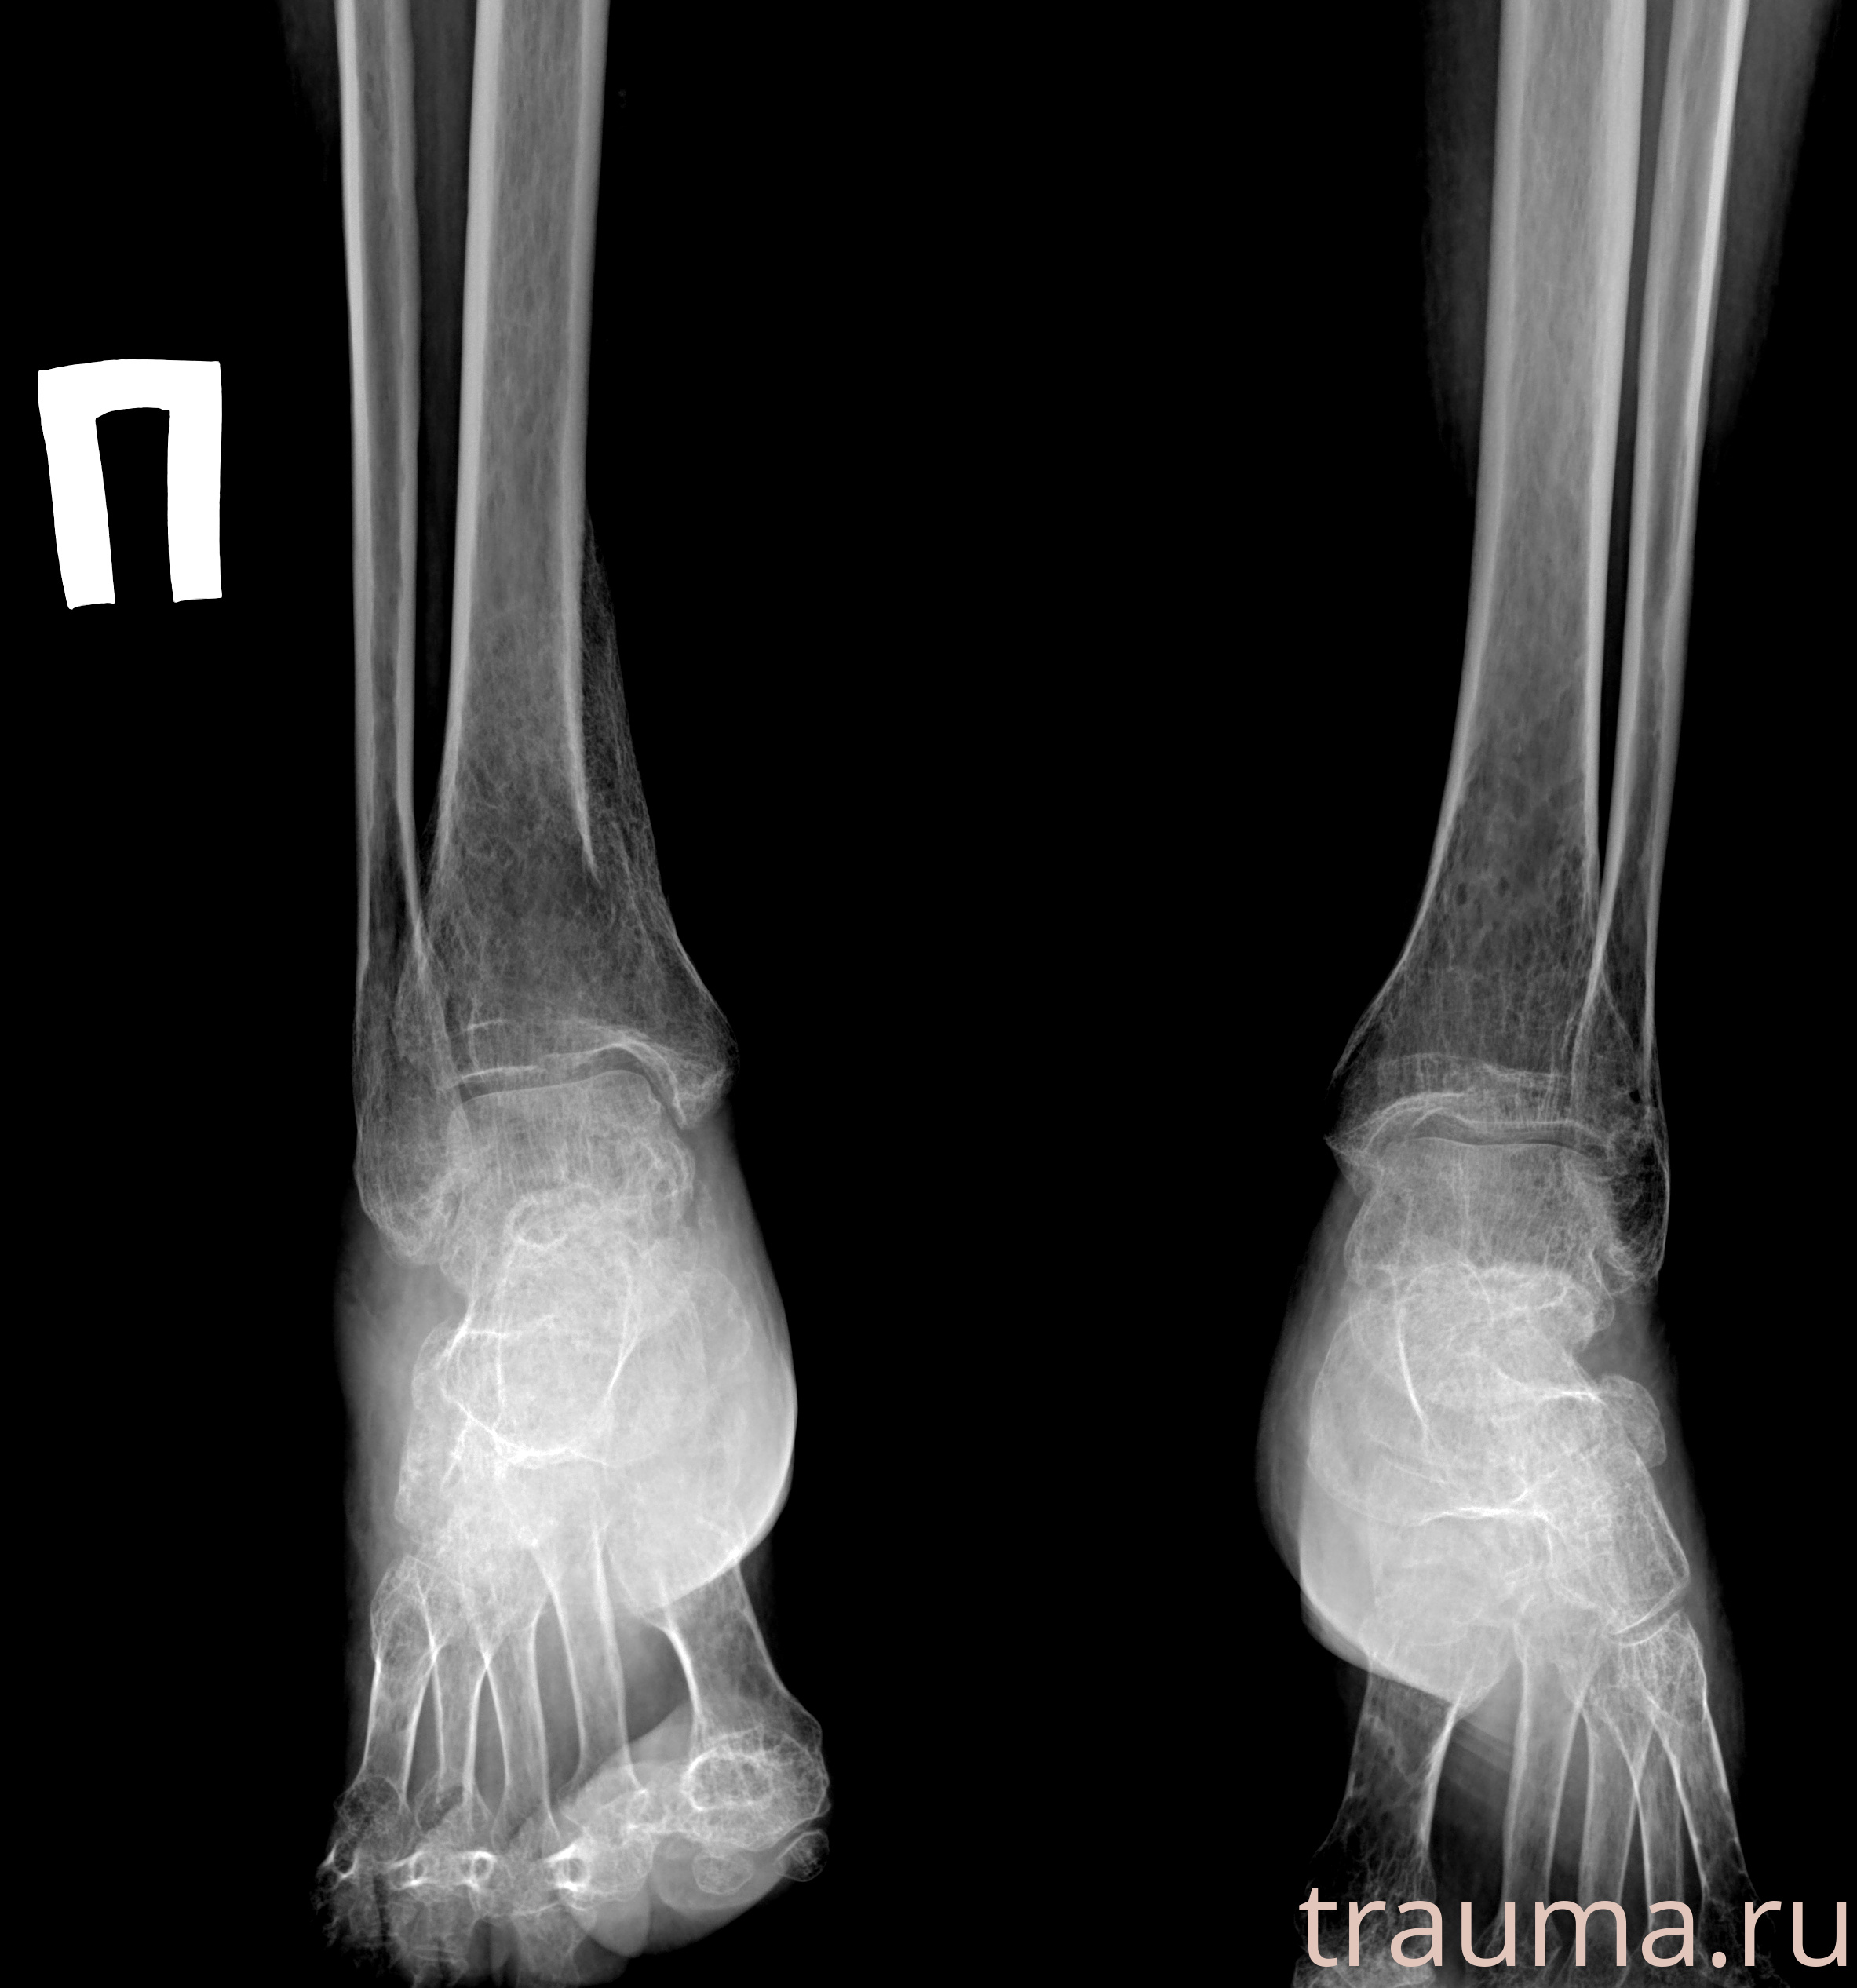

Рентген на дому: по вашему адресу приезжает врач-рентгенолог, травматолог-ортопед с мобильным рентгеновским аппаратом, проводит диагностику травмы или заболевания, делает необходимые рентгенограммы, дает рекомендации по дальнейшему лечению. Получить качественные снимки в домашних условиях возможно благодаря уникальной методике, разработанной МосРентген Центром для института  Склифосовского